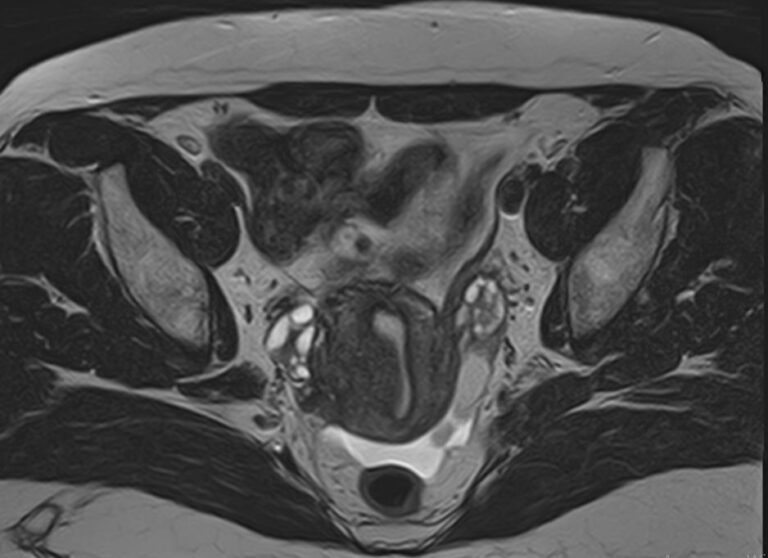

В нашей клинике магнитно-резонансная томография матки проводится при помощи новейшего томографа экспертного уровня TOSHIBA VANTAGE TITAN 1,5 Тесла. Высокая индукция магнитного поля томографа обеспечивает превосходную четкость и детализацию изображений органов женской репродуктивной системы. Отсутствие вредного рентгеновского излучения делает процедуру безопасной и дает возможность проведения исследования неоднократно по мере необходимости.

• Эндометриоз и его характер. МРТ матки и яичников обнаруживает также признаки распространения эндометриоидных очагов в область придатков и шейки.

• Новообразования тела и шейки органа (миома, саркома и др.), признаки их возможной злокачественности или доброкачественности. В «Мы и Дети» можно сделать МРТ матки по доступным ценам, решив с помощью одного исследования множество диагностических вопросов и выиграв время для эффективного лечения.

Наиболее часто томографию матки применяют в комплексной диагностике и лечении новообразований. Процедура позволяет с высокой точностью определить локализацию, размеры и влияние опухоли на окружающие ткани, а также провести первичную дифференциацию добро- и злокачественных структур (по форме, строению, особенностям накопления контраста и пр.). Динамический контроль методом МРТ позволяет объективно оценить эффективность терапевтической тактики.